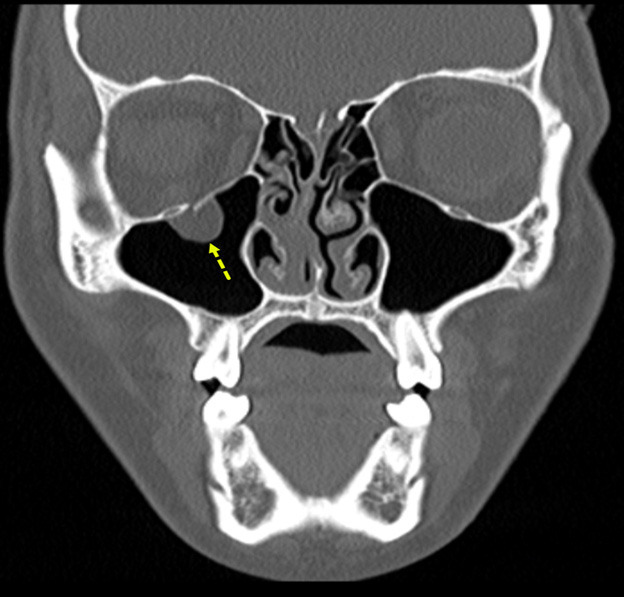

Figure 5 shows an example of an orbital floor fracture without evidence of entrapment in a pediatric patient in the coronal plane. In comparison, Figure 6 shows an entrapped orbital floor fracture in the bone window. The image reveals evidence of a non-displaced orbital fracture with entrapped intra-orbital fat.

Figure 5. Orbital Floor Fracture Without Evidence of Entrapment |

![]() |

The image shows a displaced orbital floor fracture with no evidence of entrapment. Image courtesy of Mantosh S. Rattan, MD, Radiologist, Orlando Health Arnold Palmer Children’s Hospital, Orlando, FL. |

Figure 6. Entrapped Orbital Floor Fracture |

The image shows evidence of a non-displaced orbital fracture with entrapped intra-orbital fat (bone window). Image courtesy of Mantosh S. Rattan, MD, Radiologist, Orlando Health Arnold Palmer Children’s Hospital, Orlando, FL. |